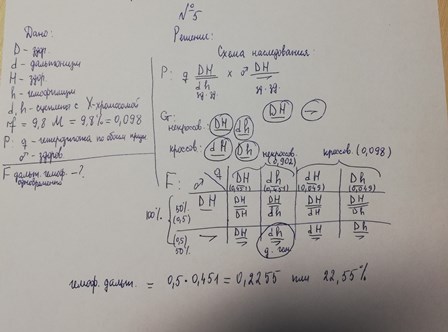

Генетика гемофилии: рецессивные гены и их проявления